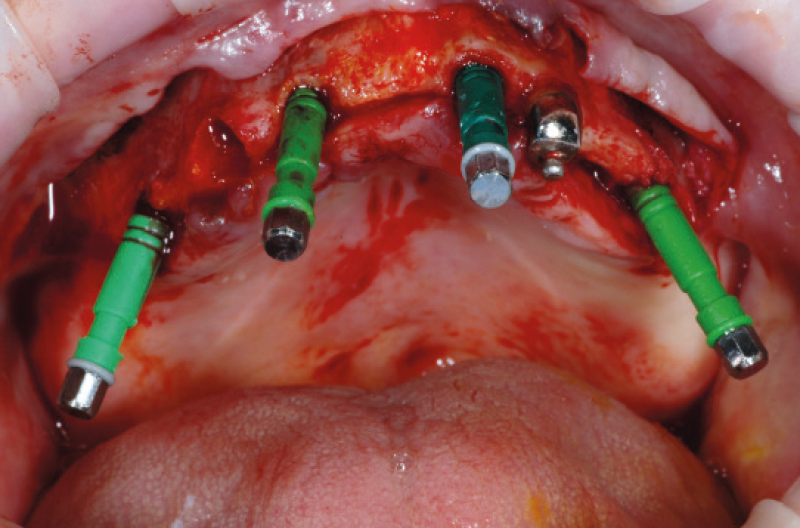

Fig. 4 – Tre impianti XCN® Narrow Ø 2,9 L 14 e un impianto Max Stability Ø 3,75 L 14 mm in posizione

A titolo esemplificativo si riporta un caso di riabilitazione implantoprotesica di un’arcata superiore di una signora di 65 anni con pochi elementi dentali non più recuperabili. L’esame Cone Beam evidenzia uno scarso volume osseo in senso vestibolo-palatale, una buona altezza ossea, oltre a una scarsa qualità ossea (Figg. 1a-c). Si pianifica di conseguenza l’inserimento di 4 impianti di piccolo diametro, a carico differito: tre impianti XCN® Narrow Ø 2,9 L 14 mm e un impianto XCN® Max Stability Ø 3,75 L 12 mm, due centrali assiali e due distali inclinati lungo la parete anteriore del seno mascellare. Dopo 6 mesi si effettua la riapertura degli impianti e, dopo aver inserito i monconi MUA più idonei e preso un’impronta di posizione dei MUA già definitivamente fissati in bocca, si realizza la protesi “Tutto su quattro” con una struttura di supporto in titanio di alta precisione (Figg. 2-10).